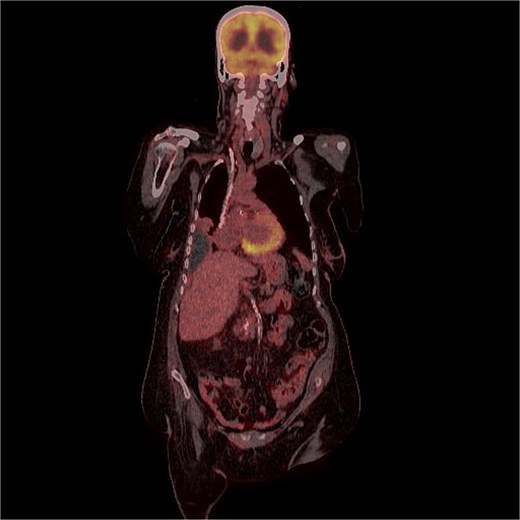

A 70-years old female came to the tertiary hospital, with a gradually enlarging right frontal-temporal scalp swelling associated with headache. She presented to the ER with abnormal movement, described by the son was gazing upward toward specific point with right upper limb jerky movement lasting for 15 s and frothy secretions, not responding during the event. Whole event lasted for 40–45 s. No reported pre-event symptoms and for post event patient was back to baseline after one-to-one hour and half. The son noticed this event repetitively happens on exertion, positioning the patient from lying to siting position, and before the dialysis sessions. Regarding her surgical and medical history, she is a known case of type 2 diabetes mellitus, hypertension, end-stage renal disease on dialysis, and cardiac disease with low ejection fraction. In addition, the patient had undergone a total abdominal hysterectomy with bilateral salpingo-oophorectomy under spinal anaesthesia in for endometria carcinoma, stage IB, grade 2 and subsequently received vaginal vault brachytherapy. Upon physical examination, the patient was noted to have a large, non-tender, soft to firm swelling in the right frontal-temporal region, with no other remarkable findings. CT with contrast (Figs 1 and 2) of the brain revealed metastasis to the right frontal bone and the greater wing of the sphenoid, with large extra-cranial and small intracranial soft tissue components with no parenchymal brain lesions were observed. A brain biopsy confirmed that there was fibromuscular and adipose tissue with focal necrosis and atypical cells, with crushed and scarse atypical cells likely neoplastic or reactive. Also, PET CT scan (Figs 3 and 4) confirms that there was brain metastasis sparing lymph nodes. Given her poor status and significant comorbidities, she was deemed unfit for systemic chemotherapy. The patient received palliative radiotherapy to the scalp lesion 20 Gy in 5 fractions.

FDG uptake was noted in the scalp lesion, while no other areas of abnormal uptake were identified elsewhere.

Most patients present with localized disease, with nearly 20% showing regional spread and 9% exhibiting distant metastases. According to the Surveillance, Epidemiology, and End Results database and other studies, 5-year survival rates are stage-dependent. The 5-year survival rate in early-stage EC exceeds 95%, but it drops to 56%–69% in patients with loco-regional spread and plummets to 17%–20% in patients with distant metastases [4]. The median age for bone metastasis is 60 [2]. According to a systematic review study, there were 40% of cases with isolated brain metastasis without extracranial metastasis, 23% cases with isolated brain metastasis with extracranial metastasis, 9% with multiple brain metastasis without extracranial metastasis, and 28% with multiple brain metastasis with extracranial metastasis [2]. These results suggest that brain metastasis is very rare and the pathogenesis is not clear enough even in our case. A patient with recurrent endometrial cancer can initially present with an isolated scalp lesion and may have a normal pelvic exam. Thus, extensive metastatic evaluation is needed in these cases to rule out any other primary site [5]. Thus, this indicates that a whole-body imaging technique, such as a fluorodeoxyglucose positron emission tomography/computed tomography (F-FDG PET/CT) scan, is useful in detecting distant or atypical metastases and in guiding the diagnosis [6]. Often cutaneous metastasis from endometrial carcinoma reflects advanced spread. The sculp although highly vascular, is an uncommon site of metastasis. Its presence usually indicates disseminated disease and is associated with a poor prognosis with most patients surviving a few months after diagnosis [3]. Furthermore, according to a case report study in literature done in 2018, there are low and high grades of endometrial stromal sarcoma, and they are divided based on gene rearrangement, also the low grade can transfer to a high grade over time which will metastasis to the scalp as in this case [7].